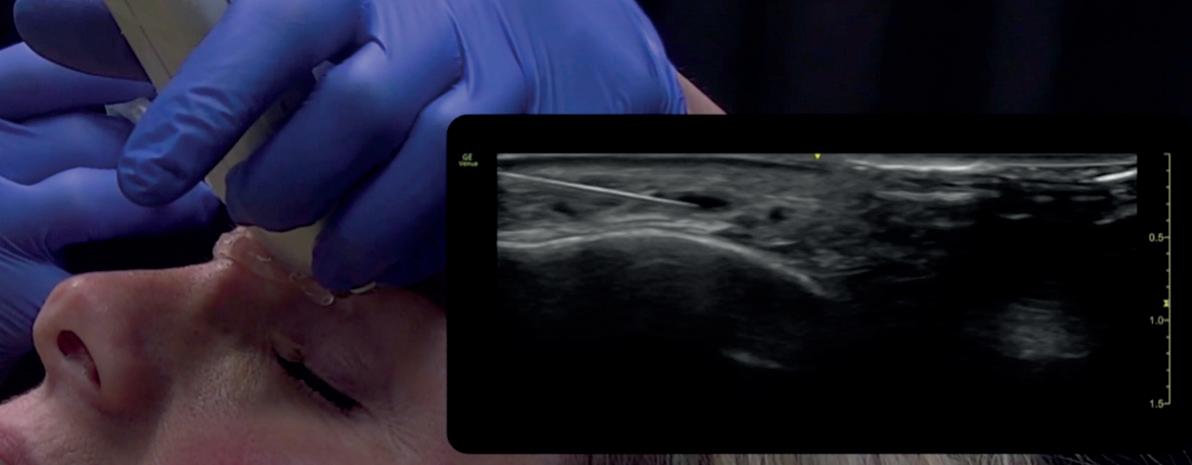

38 Case Study: Utilising Ultrasound

Dr MJ Rowland-Warmann shares a case using ultrasound when addressing a dermal filler complication

Dr MJ Rowland-Warmann is the founder and lead clinician at Smileworks clinic in Liverpool. She holds an MSc in Aesthetic Medicine and has a special interest in the management of complications. She is a KOL for Clarius Mobile ultrasound and GE Healthcare Ultrasound.